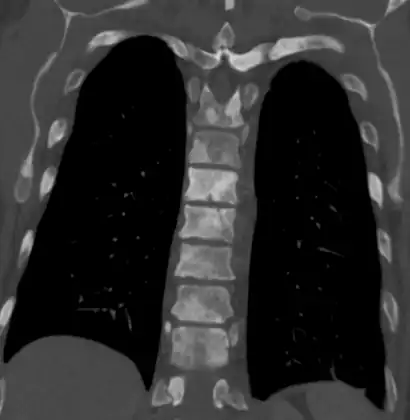

MRI Organ-confined prostate cancer

Bony metastases from prostate cancer

The most important distinction made by any staging system is whether the cancer is confined to the prostate. In the TNM system, clinical T1 and T2 cancers are found only in the prostate, while T3 and T4 cancers have metastasized. Several tests can be used to look for evidence of spread. Medical specialty professional organizations recommend against the use of PET scans, CT scans, or bone scans when a physician stages early prostate cancer with low risk for metastasis.[95] Those tests would be appropriate in cases such as when a CT scan evaluates spread within the pelvis, a bone scan looks for spread to the bones, and endorectal coil magnetic resonance imaging evaluates the prostatic capsule and the seminal vesicles. Bone scans should reveal osteoblastic appearance due to increased bone density in the areas of bone metastasis—the reverse of what is found in many other metastatic cancers.

Sclerosis of the bones of the thoracic spine due to prostate cancer metastases (CT image)